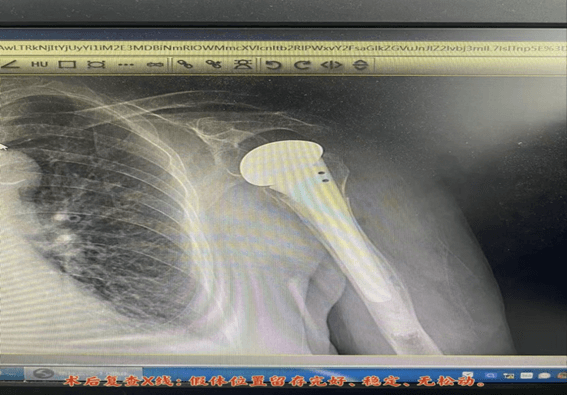

手术团队选择了经典的三角肌胸大肌间隙入路。术中,在完成截骨、扩髓、精准放置假体等关键步骤的同时,尤为注重 肩袖结构(特别是大结节)的解剖复位与重建,这是保障术后肩关节功能恢复的核心所在。